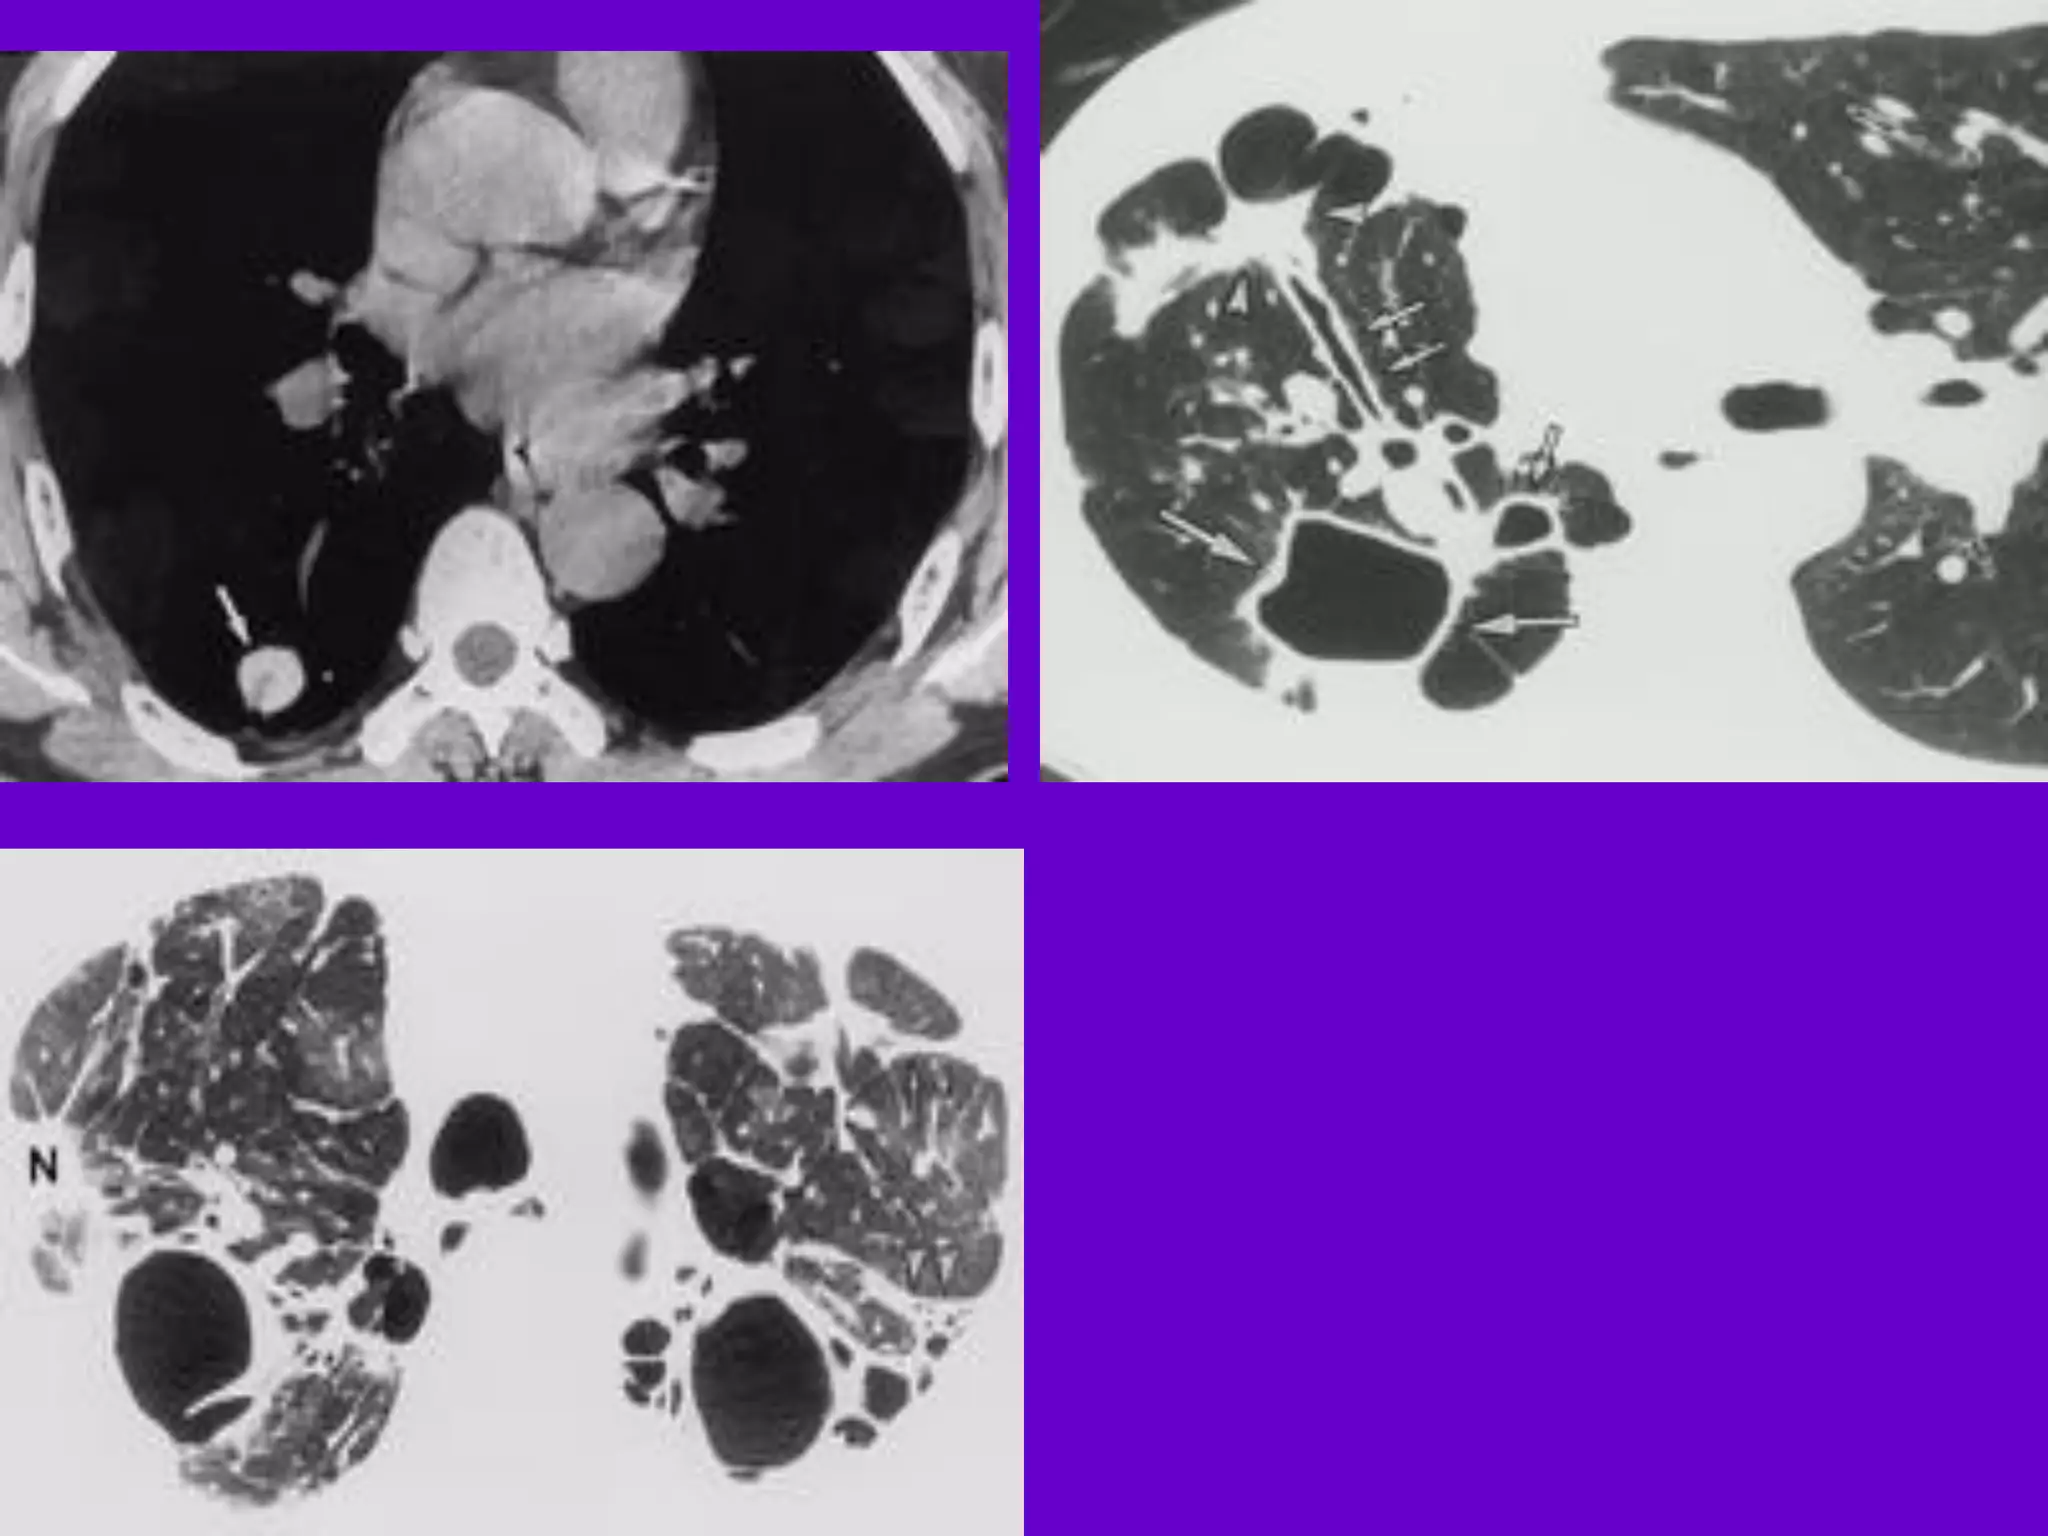

CT Scan andMRI Scan in the diagnosis of TB 􀂄 The advent of CT and MRI imaging in the last two decades has redefined the approach in analysis of various diseases including TB.* 􀂄 CT and MRI have shown several advantages over conventional radiology in early diagnosis and follow-up of TB in different parts of the body. *Buxi TBS Indian J Pediatr 2002;69:965-972

Pulmonary TB : LobarPneumonia 􀂄 CT is superior than plain CXR in picking up the consolidation, atelectasis and the hilar LN thereby making the diagnosis easy. 􀂄 MRI reveals some of these changes, however, CT is the diagnostic modality of choice in such cases. 􀂄 Bronchopneumonia 􀂄 On CT it is usually B/L and widespread, not always symmetrical involvement of lungs. 􀂄

Hilar and Mediastinal Lymphadenopathy CTand MRI depict the hilar and mediastinal LN equally well. 􀂄 Calcification in the nodes is however better seen on CT. 􀂄 Necrosis is seen as focal areas of low attenuation on a CECT. 􀂄 On MRI focal necrosis is seen as areas of increased signal intensity on T2W images. 􀂄 EBTB 􀂄 HRCT is sensitive in the detection of early endobronchial spread of disease. 􀂄

Miliary TB 􀂄 Earliestform of miliary TB is detectable on HRCT. 􀂄 Coalescing nodules result into patchy irregular opacities and HRCT shows this variation effectively and has been described as “snowstorm appearance”. 􀂄 HRCT shows cavitation, which is not evident on plain CXR. Pleural Effusion 􀂄 􀂄 CT is sensitive to diagnose and define even minimal pleural effusion/pleural calcification. 􀂄 Pleural fluid is seen on inversion recovery MR images as areas of increased signal intensity along the inner aspects of the chest wall.

Skeletal TB Pott’s Disease(vertebral TB) 􀂄 CT and MRI helps in demonstrating a small focus of vertebral body involvement and defining the extent of the disease. 􀂄 CT/MRI help to evaluate TB involving the craniovertebral junction, sacro-iliac joint and posterior appendages. 􀂄 They are also helpful in assessment of spinal canal encroachment , posterior element involvement and in deciding the surgical approach. 􀂄

GIT TB Strictures ofthe small bowel, mucosal edema and thickening are well visualized on CT. 􀂄 MRI depicts the para-aortic, aortocaval and mesentric lymph nodes effectively. 􀂄 GUT TB 􀂄 Various patterns of hydronephrosis may be seen at MR urography. 􀂄 MRI helps to differentiate macronodular TB lesions from the other mass lesions. 􀂄